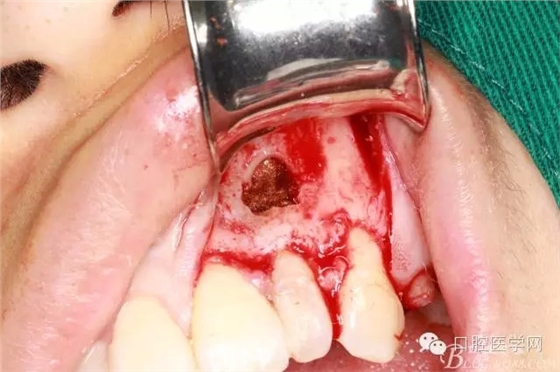

翻全厚瓣(-)

翻全厚瓣(二)

翻全厚瓣后暴露骨面

確定根長(根管充填時已確定)